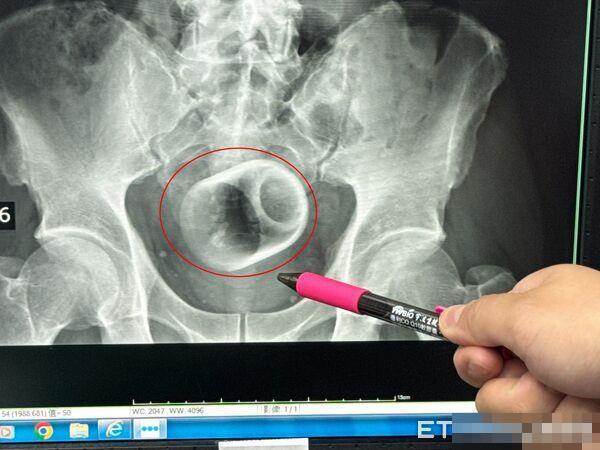

中部一名男子腹脹三天無法大便,肚子痛到受不了,趕緊到李綜合醫院求診,醫師透過X光檢查,驚見患者的肛門竟然塞一個直徑約6公分、高約8公分的陶瓷杯,原本要用器械夾出杯子,但杯緣光滑無法施力,杯子全被大腸包住,部分腸子缺血也造成壞死,最後全身麻醉「開腸破肚」的才順利取出杯子。

▲▼臺中男子3天無法解便,竟是肛門塞了瓷杯。(圖/李綜合醫院提供,下同)